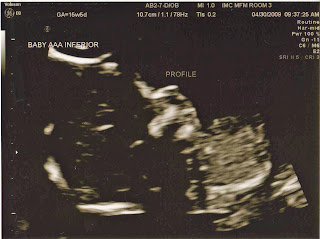

Just what my husband and I were hoping for! We can't believe it! We did get ultrasound pictures of each of the babies genders but they're really dark. I don't know why we keep getting really horrible ultrasound pictures. I'll post them anyway...I don't know how many of you will be able to understand them but it'll be fun to see just the same.